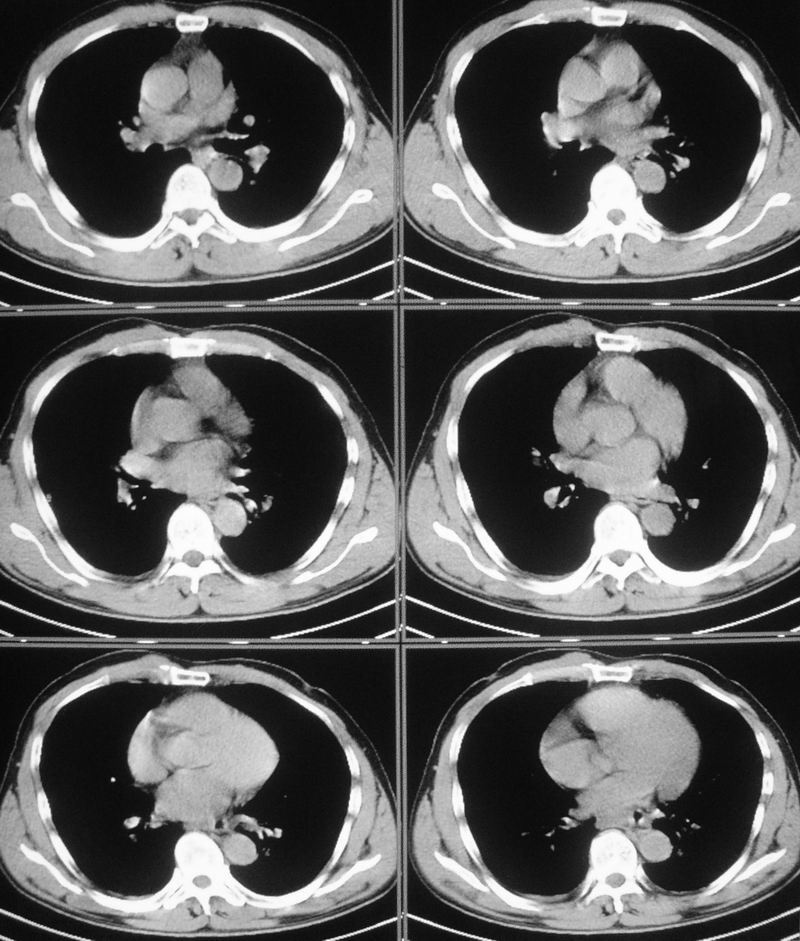

男性,47岁,车祸致胸痛2小时。

请大家看看后纵隔食道及降主动脉周围的软组织密度灶是什么?双侧膈肌脚内侧及椎管内的气体影是怎么回事?

结合病史多考虑纵隔血肿形成

有外伤病史,两个征象应该认为是外伤所致出血;需再确认是否有骨折,导致的积气。

是后纵隔出血还是出血合并有胸主动脉加层,增强扫描.

结合病史多考虑纵隔血肿形成 ,椎管及右侧腰大肌内侧气体影也与外伤有关。

要不要考虑食道中下段的损伤呢?这样血肿和气体影就都好解释了。